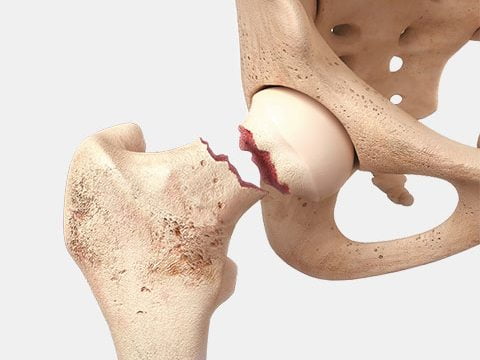

На фоне такой активности или в силу патологий опорно-двигательного аппарата сустав изнашивается, терпит дистрофические изменения. Пациент жалуется на боли, снижается двигательная активность, ухудшается качество жизни. Может случиться и перелом шейки бедра.

Основным эффективным и адекватным методом терапии является эндопротезирование ТБС — замена разрушенного суставного соединения на имплантат.